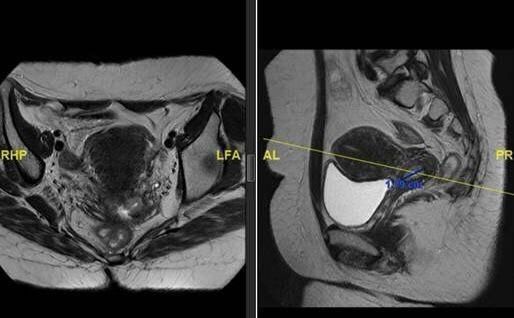

تمكن فريق طبي في مدينة الملك فهد الطبية إحدى مكونات تجمع الرياض الصحي الثاني من إدخال المعالجة الحديثة و استحداثها لأول مرة في المملكة لعلاج ورم متقدم في عنق الرحم يبلغ حجمه تقريبا 8 سم لمريضة في العقد الخامس من عمرها باستخدام التقنية الحديثة بمساعدة العلاج الإشعاعي التداخلي المعقد  انترستيشيل

وأوضح رئيس الفريق المتخصص في العلاج الإشعاعي التداخلي المعقد  الاستشاري سعد الرشيدي أن هذه التقنية تستخدم لمعالجة أغلب أورام النساء  المعقدة وخاصة عند رجوعها  في الحوض بما فيها الأورام المتقدمة جدا حيث يتم زرع القسطرة داخل الورم لإيصال جرعات إشعاعية عالية للقضاء على الورم والتي لا تتم بالطريقة التقليدية.

وأضاف د. الرشيدي أن هذه التقنية تحتاج إلى تدريب عالي الدقة ولا توجد حاليا إلا في دول شمال أمريكا و أوروبا وتحتاج المعالجة بهذه التقنية إلى مركز متكامل ومتخصص بهذا العلاج حيث يتم تقييم المريض في العيادة ومن ثم عمل الفحوصات الأشعات التي تتضمن الرنين المغناطيسي ويبدأ المريض في العلاج الإشعاعي الخارجي والكيماوي لعدة جلسات تتبعها هذه التقنية الحديثة.